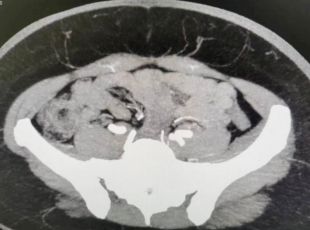

不久前,我院超级显微外科门诊接诊了一位乳腺肿物的患者。徐女士一年前无意间发现左乳有个小硬块,约花生米大小,但没有疼痛和任何不适感,想着那么年轻,抱着侥幸心理,没有就诊。6个月前发现肿物明显变大了,腋窝好像也能触及硬结,经过乳腺超声、穿刺病理检查确诊乳腺癌且考虑淋巴结转移。

患者一下慌了神,传统的手术需要把乳房完全切除同时行腋淋巴结清扫术,术后就只剩一个乳房和一道丑陋的疤痕了。患者不能接受,听说我院可以切除肿瘤同时重建乳房,为此慕名而来。为确保患者手术顺利进行,就需要多个科室联合会诊,专家团队对此病例进行了严谨的病例讨论与研究。

手术方案为左乳腺癌改良根治+游离腹壁下动脉穿支皮瓣修复术